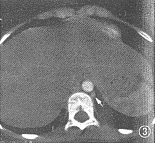

图1~6 为同一病例,部分型肺静脉异位连接(心脏型)。图1示右上肺静脉(短箭头)引流入右心房(RA),左上肺静脉(长箭头)引流入左心房(LA),房间隔缺损巨大。图2示两下肺静脉(箭头)分别引流入左右心房。RV:右心室;LV左心室。图3示下腔静脉肝段缺如:肝脏水平未见下腔静脉显影,半奇静脉粗大(箭头)。图4为表面阴影显示法三维重建,示右侧上下肺静脉(白箭头)均引流入右心房,左侧上下肺静脉(黑箭头)均引流入左心房。SVC:上腔静脉。图5为导管自下腔静脉经奇静脉入右心房经右心室至右肺动脉造影:右肺静脉(黑箭头)引流入右心房(白箭头)。图6为左肺动脉造影,示左肺静脉(白箭头)引流入左心房(白三角箭头),对比剂经房间隔缺损(黑箭头)分流入右心房

2例手术患者,完全型及部分型肺静脉异位连接各有1例。其中部分型肺静脉异位连接者EBCT显示右侧肺静脉引流入右心房,而左侧肺静脉正常回流入左心房,伴有II孔型房间隔缺损、肺动脉高压、下腔静脉肝段缺如。术前心血管造影检查及手术所见均与EBCT相同(图1~6)。1例完全型肺静脉异位连接,术前造影示单发右位心、右室双出口、肺动脉瓣及瓣下狭窄、房室间隔缺损、双上腔静脉,但心室造影未能明确肺静脉引流位置,遂行EBCT检查。EBCT除显示上述畸形外,尚显示右位主动脉弓及完全型肺静脉异位连接。